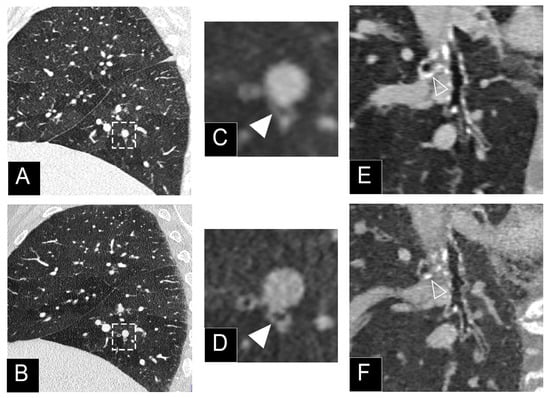

3.2. Nodule Imaging

- Si-Mohamed, S.A.; Greffier, J.; Miailhes, J.; Boccalini, S.; Rodesch, P.A.; Vuillod, A.; van der Werf, N.R.; Dabli, D.; Racine, D.; Rotzinger, D.; et al. Comparison of image quality between spectral photon-counting CT and dual-layer CT for the evaluation of lung nodules: A phantom study. Eur. Rad. 2021, in press. [Google Scholar] [CrossRef] [PubMed]

- Zhou, W.; Montoya, J.; Gutjahr, R.; Ferrero, A.; Halaweish, A.; Kappler, S.; McCollough, C.; Leng, S. Lung nodule volume quantification and shape differentiation with an ultra-high resolution technique on a photon-counting detector computed tomography system. J. Med. Imaging 2017, 4, 043502. [Google Scholar] [CrossRef]

- Kopp, F.K.; Daerr, H.; Si-Mohamed, S.; Sauter, A.P.; Ehn, S.; Fingerle, A.A.; Brendel, B.; Pfeiffer, F.; Roessl, E.; Rummeny, E.J.; et al. Evaluation of a preclinical photon-counting CT prototype for pulmonary imaging. Sci. Rep. 2018, 8, 17386. [Google Scholar] [CrossRef]